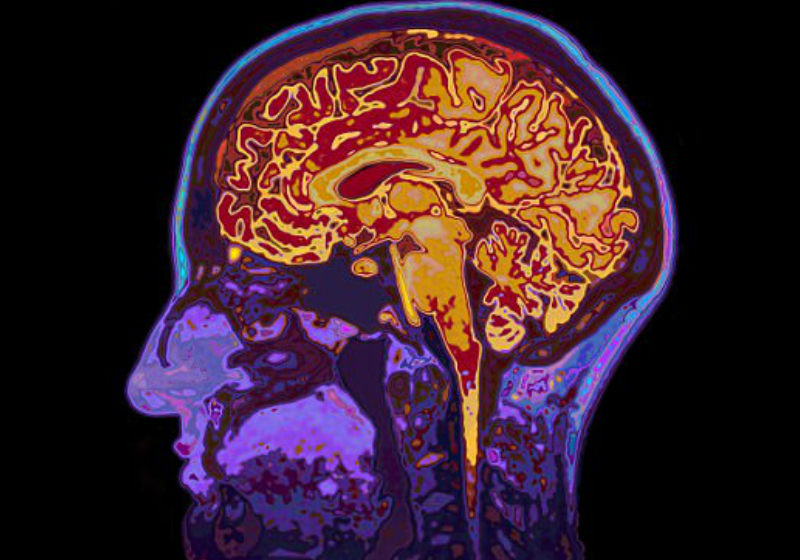

Pela primeira, vez exames cerebrais mostram que comer salmão, cavala e sardinhas previne a doença de Alzheimer.

Os ácidos graxos ômega-3, encontrados no peixe oleoso, fazem aumentar a circulação de sangue nas regiões cerebrais que controlam a memória e aprendizagem – destruídas pelo distúrbio neurológico.

As varreduras determinam a atividade cerebral medindo o fluxo sanguíneo.

Os resultados, publicados no Journal of Alzheimer’s Disease, mostraram que as pessoas com níveis elevados de ômega-3 têm mais sangue fluindo para as regiões cerebrais associadas à memória e aprendizado.

Eles também são melhores na aquisição e compreensão do conhecimento e que a saúde mental e emocional é mais forte naqueles com altos níveis de omega-3.